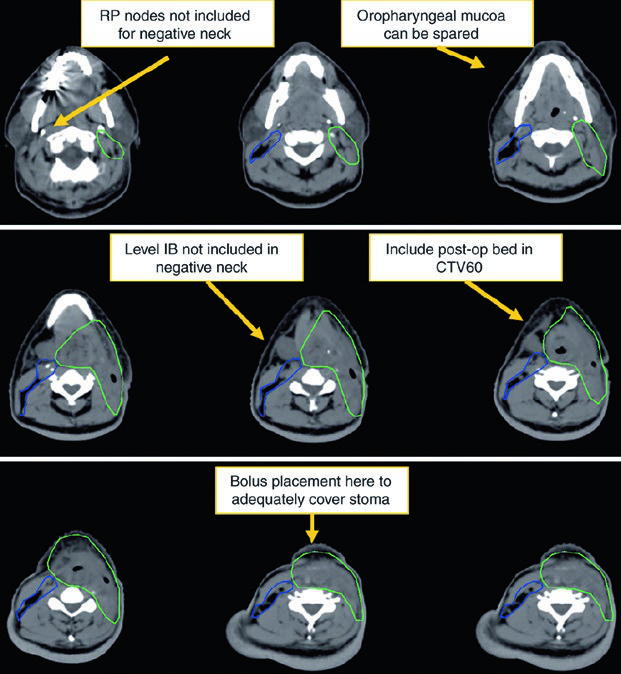

Patients should be simulated supine with a head rest, neck extension, and a five-point custom Aquaplast mask that immobilizes the head, neck, and shoulders. A shoulder pull board can be added when shoulder position interferes with beam entry.

Patients with extensive dental metal may benefit from a custom mouthguard to absorb electron scatter and reduce mucositis. CT simulation should use intravenous contrast, slice thickness of 3 mm or less, and coverage from the vertex through the carina. The isocenter is usually placed at the arytenoids unless there is subglottic or hypopharyngeal extension, in which case it moves 1 cm inferiorly.

In postoperative cases, placing a radiopaque marker over the scar is helpful. For daily image guidance, the preferred approach is daily cone beam CT aligned to the larynx. Daily kilovoltage imaging to bony anatomy plus weekly cone beam CT is also acceptable. Patients should be instructed not to swallow during simulation, IGRT, or treatment delivery.

If the anterior commissure is involved, bolus and anterior flash are not optional refinements. They are part of getting superficial coverage right.

The figure caption adds two good reminders. In that example, level IB was included by the treating physician even though it can be omitted. The upper trachea was not treated, but the text notes that it should be included when indicated. That is a useful warning against copying a figure without rechecking the anatomy.

Postoperative radiation

Postoperative treatment is driven by adverse pathologic features. The chapter lists positive or close margins, extranodal extension, pT4 primary disease, pN2-pN3 nodal disease, perineural invasion, vascular invasion, and lymphatic invasion, citing NCCN v.2020. Concurrent chemotherapy should be added for extracapsular extension or positive margins.

The high-risk postoperative CTV receives 60 Gy and should include the operative bed, scar, stoma, and dissected node-positive neck. Positive margins or extracapsular extension may justify a boost to 66 Gy. The undissected node-negative neck may be included as a low-risk CTV to 54 Gy. If there is subglottic extension or an emergent tracheostomy, the stoma may also be boosted to 66 Gy. The chapter makes the anatomy explicit: a stomal recurrence is a tracheoesophageal node recurrence.